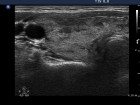

Follow-up examinations (rows from 1st to 8th):

17.2 |

10 mg methimazole |

1.92 |

15.9 |

6.0 |